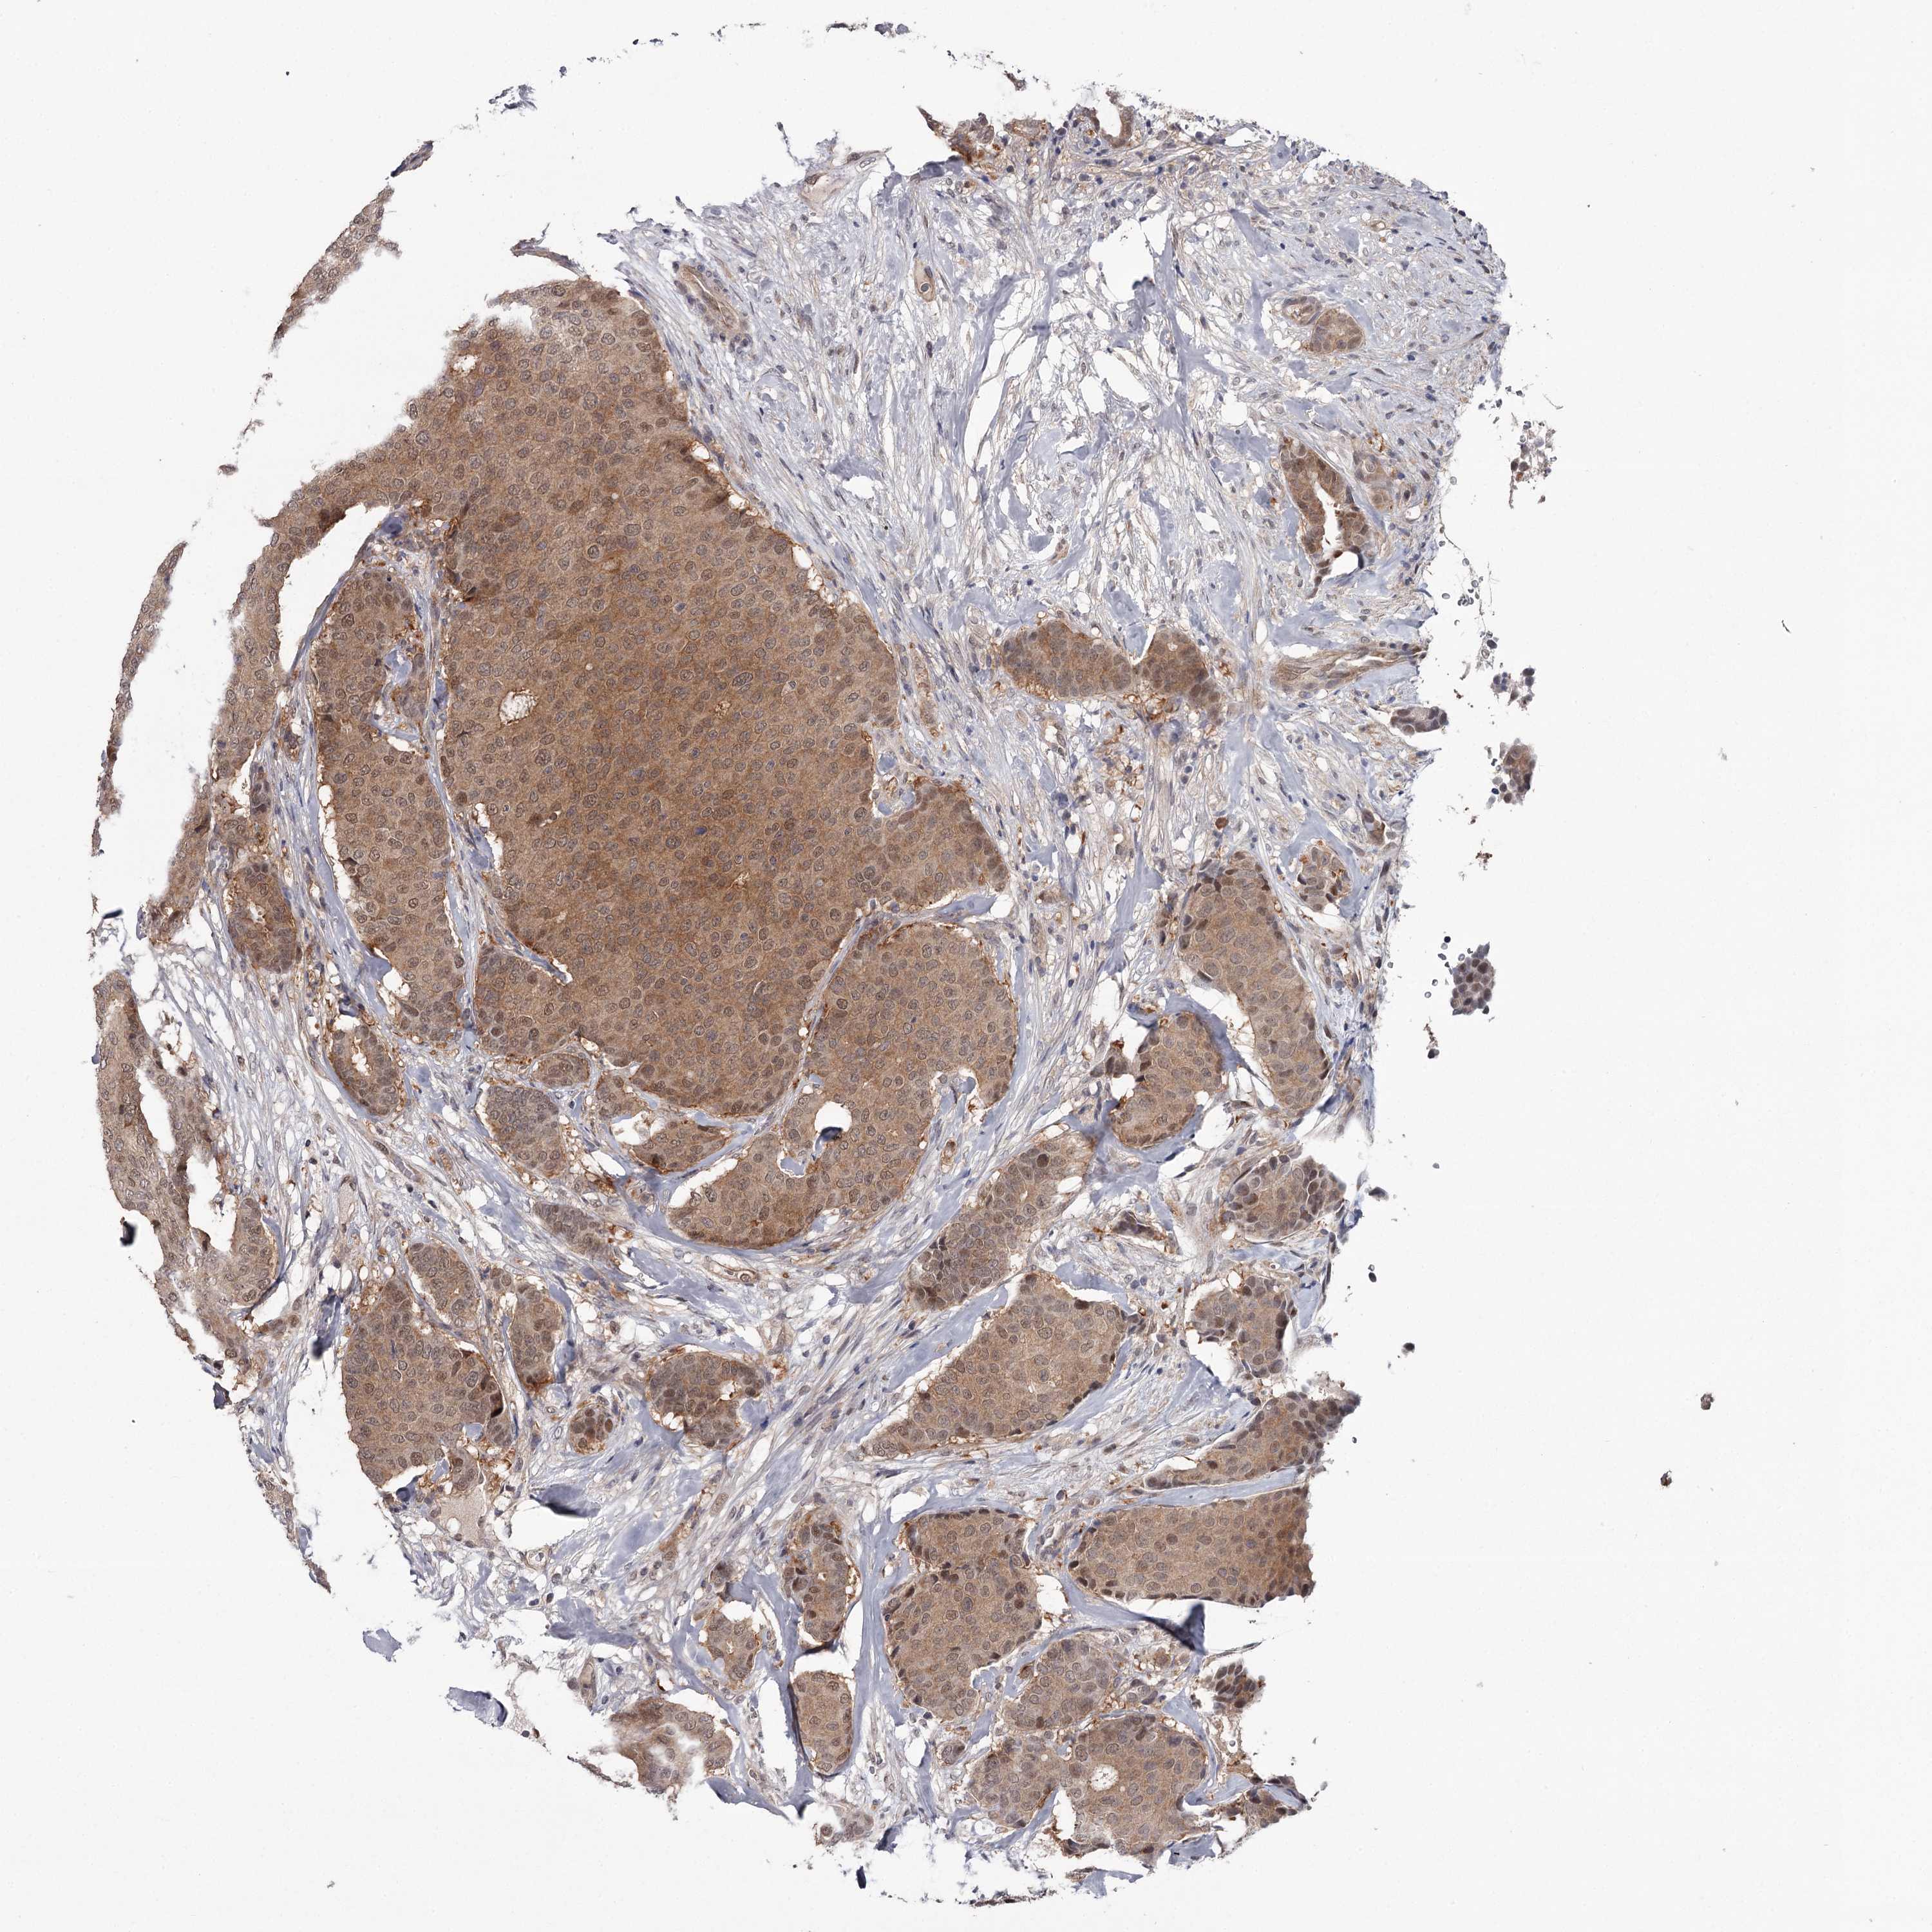

CANCER BREAST CANCER Show tissue menu

BRCA TCGA BRCA VALIDATION PROTEIN EXPRESSION